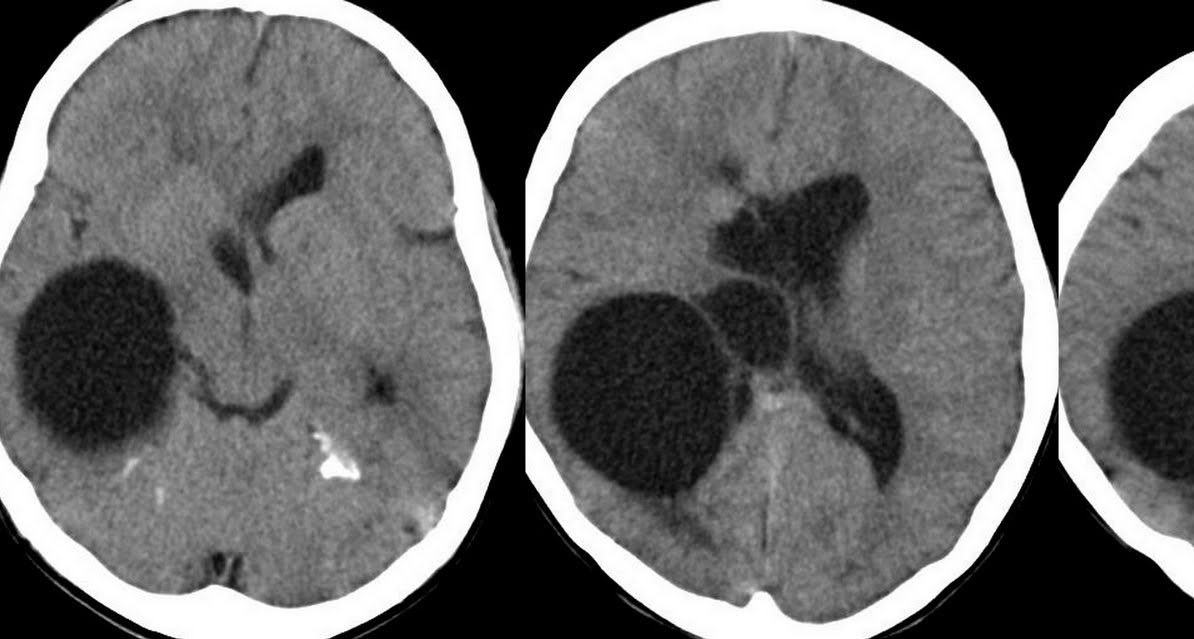

Porencefalia - Vídeo de Ultrassom